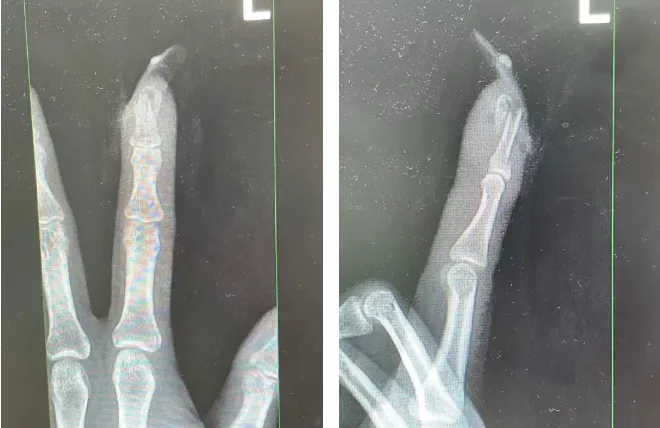

王女士受伤手指的X光影像。图源:杭州市临平区中西医结合医院

经检查

王女士指甲断裂

局部甲床外露

医生表示假如没有美甲

伤害不会这么严重